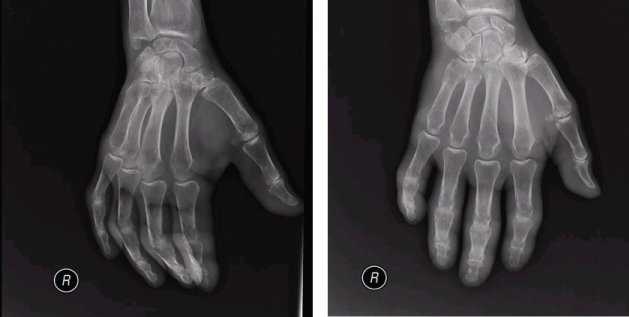

Chest radiography had an opacity on right hemithorax, on the lung base (Figure 1). The patient also performed a hands radiography that revealed no erosions (Figure 2). A full body computerized axial tomography (CT) scan was done to exclude neoplasia revealing "hypercaptant lymph node on supra-clavicular fossa 18 × 14 mm. Alveolar condensation without the bronchogram sign, rounded with hipocaptant regions suggestive of necrosis with pleural contact on right basal pyramid. Bronchi caliber reduction. Lymph node conglomerates and hipocaptant lymph nodes pre-vascular and para-tracheal on the right. These aspects are suggestive of primary lung lesion (Figure 3).

Figure 2: Hands and wrists radiography (right hand) with no erosions. View Figure 2

With a variable clinical presentation, it often resembles to rheumatoid arthritis (RA) [2-4], particularly late-onset RA [15], however some features set them apart (Table 1). It usually has an acute, rapid onset, with asymmetrical lower extremity involvement, with no nodules or deformities [2-4]. It is accompanied by elevation of inflammatory markers (CRP and ESR), and usually seronegative for anti-citrullinated protein antibodies (ACPAs) but may be positive for rheumatoid factor and antinuclear antibodies [2,3,9]. Synovial fluid has nonspecific inflammatory changes and histology shows and nonspecific synovitis [3,4]. Radiographically, no erosions are visible [2,4]. Constitutional symptoms of weight loss, fever, enlarged lymph nodes and hepatosplenomegaly may be present [2,9]. The arthritis will most often be refractory to non-steroid anti-inflammatory drugs, corticoid therapy and disease modifying drugs [2,16], but responsive to the tumor treatment [3,6,17].